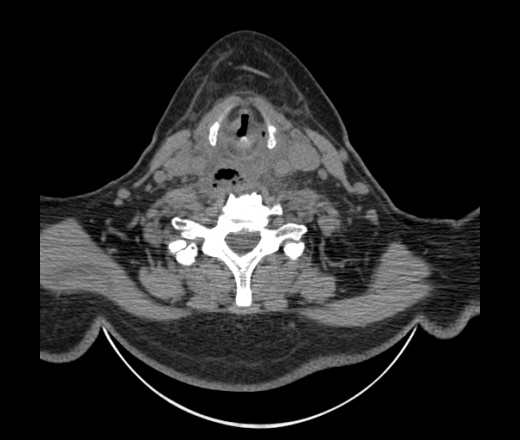

Женщина поступила в х/о спустя 4 дня после того как при употреблении карася подавилась костью.

Наличие газа в средостении на протяжении тел С2-С6 (медиастинальна эмфизема); рыбная кость на уровне тела С6.

При всем уважении, но говорить о медиастинальной эмфиземе, оценивая мягкие ткани шеи, как-то слишком резко. На мой взгляд, это ретрофарингеальное пространство.

Эвакуировали почти 100мл гноя. Но кость не смогли найти. Думаю что она даст дальнейшее ослоднение. Эндоскопически за черпалонадгортаной звязкой не смогли зайти в пищевод, все мягкие ткани отечные, просвет пищевода сдавлен. По всей видимости параэзофагеальная клетчака тоже задействована. Эмпиема, если ее можно так назвать, незнаю как правильно дошла до уровня яремной вырезки. Чем закончиться напишу. Ждем медиастинита.

Согласен с Вами; конечно, наличие газа в клетчатке ретрофарингеального пространства (затмение с опечаткой..). К сожалению, процесс "продвигается" к медиастиниту. Но почему никто, не отмечает наличие рыб. кости; или это для Всех очевидно?

Так вы уже отметили. Хотя ориентировал бы не скелетотопически, а на перстнечерпаловидный сустав.

Кость то мы сразу выявили, размеры где то 17*2мм, но ее так и не получается найти в этой каше